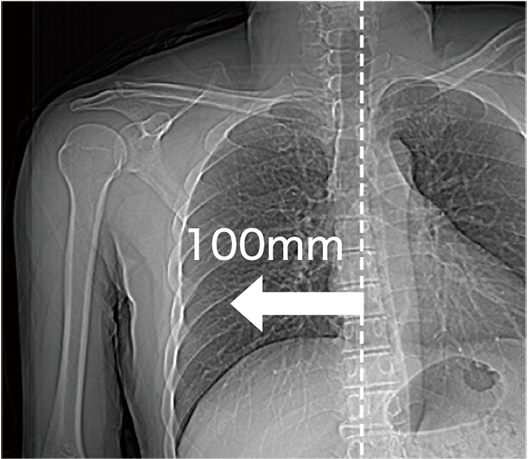

更輕鬆地定位待檢查區域

病床橫向最長可移動達 200 mm,即使在心臟或骨科(如肩部)等掃描部位,也能更容易將檢查區域置中,提高檢查效率

將心臟定位在視野中央附近

將四肢定位在視野中央附近